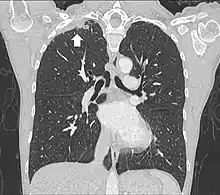

Tomodensitométrie

Le scanner thoracique permet d'analyser avec précision la localisation de la tumeur, de mesurer sa taille, et de rechercher des adénopathies médiastinales[11]. Idéalement, il doit être injecté d'un produit de contraste iodé afin de préciser les rapports vasculaires[11].

Dans le cadre du bilan d'extension, le TEP scanner aide à rechercher les localisations secondaires métastatiques et à préciser l'envahissement ganglionnaire.